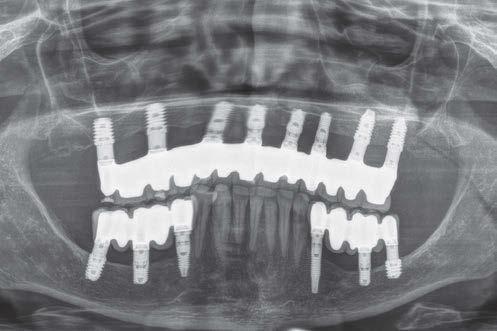

La rehabilitación del maxilar superior posterior mediante implantes dentales se ha visto condicionada clásicamente por la neumatización excesiva del seno maxilar al perderse los dientes relacionados con el mismo (dientes antrales) (1, 2). En estos casos, se pierde gran parte de la altura del reborde óseo residual generándose atrofias verticales, que pueden limitar, de forma importante, la inserción de implantes de manera directa (3-5).

seno post-extracción sea para el segundo molar o cuando se realiza la extracción del primer y segundo molar simultáneamente (6). Cuando los dientes se han perdido y el seno ha ocupado gran parte del volumen óseo residual de la zona del maxilar superior en su zona posterior, clásicamente, se realizaba una técnica de elevación de seno por abordaje lateral para, mediante un injerto óseo compuesto por diferentes materiales (hueso autólogo, biomaterial o mezcla de ambos generalmente), volver a recuperar la altura de cresta ausente y poder insertar los implantes dentales posteriormente o en el mismo procedimiento, siempre que existiese un volumen óseo residual que permitiese que los implantes quedaran estables (7-9).

como los implantes cortos, extracortos y actualmente también los ultracortos, que hacen que sea posible insertar los implantes de forma directa en volúmenes de hueso muy reducidos (alturas residuales en torno a los 5 mm), donde clásicamente se hubiese llevado a cabo una elevación de seno (10-13).

Estos implantes permiten, por lo tanto, la inserción sin técnicas accesorias en una única cirugía y con un procedimiento menos traumático para el paciente, a la vez que más predecible, al englobarse un menor número de factores quirúrgicos que pueden generar efecto negativo en el proceso (cicatrización, integración del injerto, dehiscencia y exposición del injerto, perforación de la membrana de Schneider, obstrucción del seno, etc.) (12, 13).

Aún así, existen hoy en día situaciones en las que la inserción de un implante corto o extra-corto no es posible de forma directa, cuando existe un volumen óseo residual por debajo de los 5 mm, existiendo en estos casos una nueva alternativa terapéutica a la elevación de seno convencional que es la elevación de seno transcrestal (14-15).

En esta técnica se accede a través de la cresta mediante la confección de un neoalveolo generado por fresado al seno maxilar despegándose la membrana desde este neoalveolo e insertándose el implante corto o extra-corto con o sin injerto asociado (en función del volumen en altura que se pretende ganar) (14-15).

Ya que ambas técnicas quirúrgicas siguen hoy en día en pleno auge, aunque las indicaciones para cada una de ellas han evolucionado en el tiempo, quedando la elevación convencional únicamente indicada hoy en día en aquellos casos de 1-2 mm de volumen óseo residual (donde es muy complejo estabilizar un implante corto por elevación transcrestal), creemos útil poder comparar la evolución de ambos procedimientos en el tiempo, a ser posible en un mismo paciente, donde el resto de variables que puedan afectar al seguimiento sean iguales, y, por lo tanto, la comparación sea más útil. Por ello, hemos realizado un análisis retrospectivo de pacientes en los que se han realizado los dos procedimientos, uno en cada cuadrante superior y ver la evolución en el tiempo de los implantes insertados en cada caso. Con esta idea en mente, hemos llevado a cabo un estudio retrospectivo que evaluase estos factores, y que se detallan a continuación.